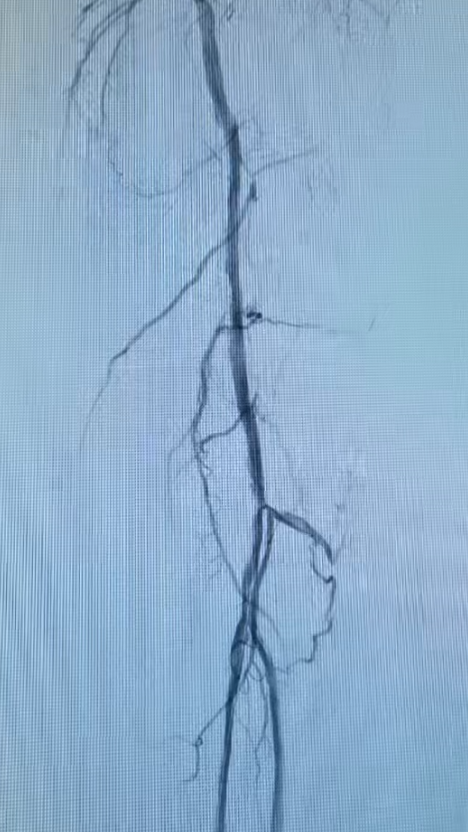

术前大腿.png

术后大腿.png

股浅动脉长段闭塞段术前(左)血流中断,术后(右)真腔成功开通